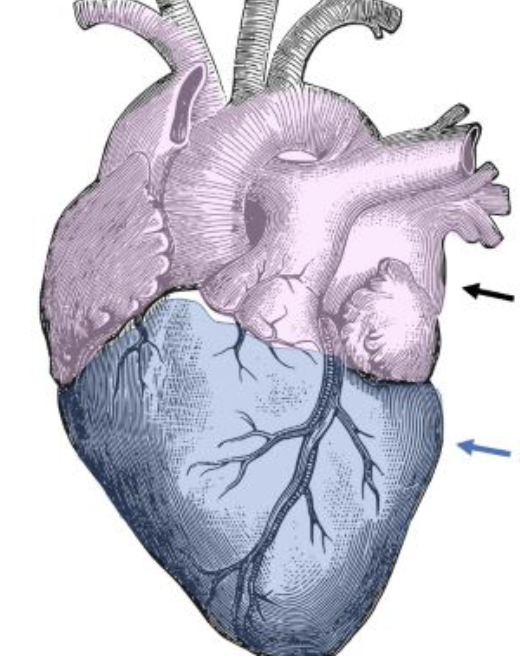

black arrow

inferior vena cava

black

pulmonary trunk

purple

left pulmonary artery

black

left pulmonary veins

blue

(branches of) right pulmonary artery

yellow

right pulmonary veins

orange

ascending aorta

purple

aortic arch